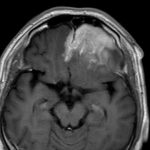

498

'23年12月

20代

下垂体卒中

頭蓋内腫瘍摘出術